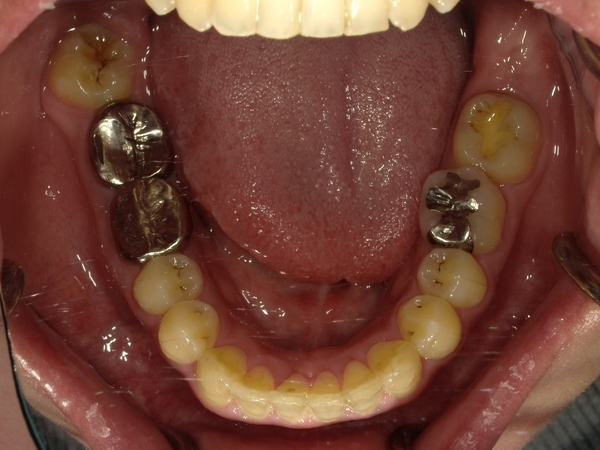

30代女性非抜歯

BEFORE→AFTER

〇ご相談内容:歯の叢生(ガタガタ)

〇矯正の種類:マウスピース型矯正「インビザラインGo」

〇治療期間:16週間

〇治療費用:44万円(税込)